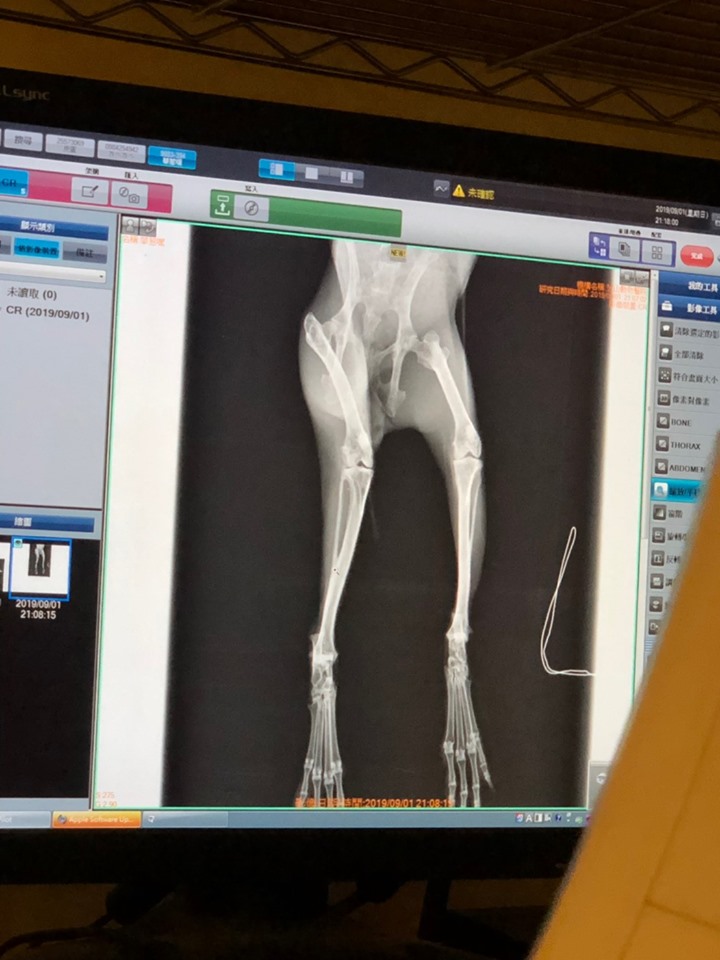

===2019/9/1初次健檢==

【華惹嘿】

救援來髒的很明顯,毛髮糾結

體重780g

應為男生,生殖器官還不太明顯,初估可能是3.4個月幼兔,還看不到蛋蛋

但是X光脊椎較密可能有擠壓,也可能是老公兔已紮,再觀察看看有沒有繼續長大掉蛋蛋⋯⋯

打結嚴重,下半身都是打結和尿,中途有剃毛清潔,左腹部有2個傷口已結痂、腳底胼胝

右腳翹起,走路怪怪的,肌力較弱,照X光後無骨折,有可能是軟組織發炎拉傷之類,先開消炎藥讓他舒服一點,要鋪軟平面活動

牙齒都不漂亮都是渣渣,要多練習吃草

二眼流淚,左眼分泌物比較多,這幾天可多幫他清潔按摩,之後再觀察

腸胃還可以,蠕動正常,大便偏小無異狀

下巴糾結多,檢查牙齒應無大礙,應不是流口水,皮膚也無發炎,可能流浪造成毛髮糾結,再慢慢清乾淨繼續觀察

瘦小髒髒,要多給他好料補身體